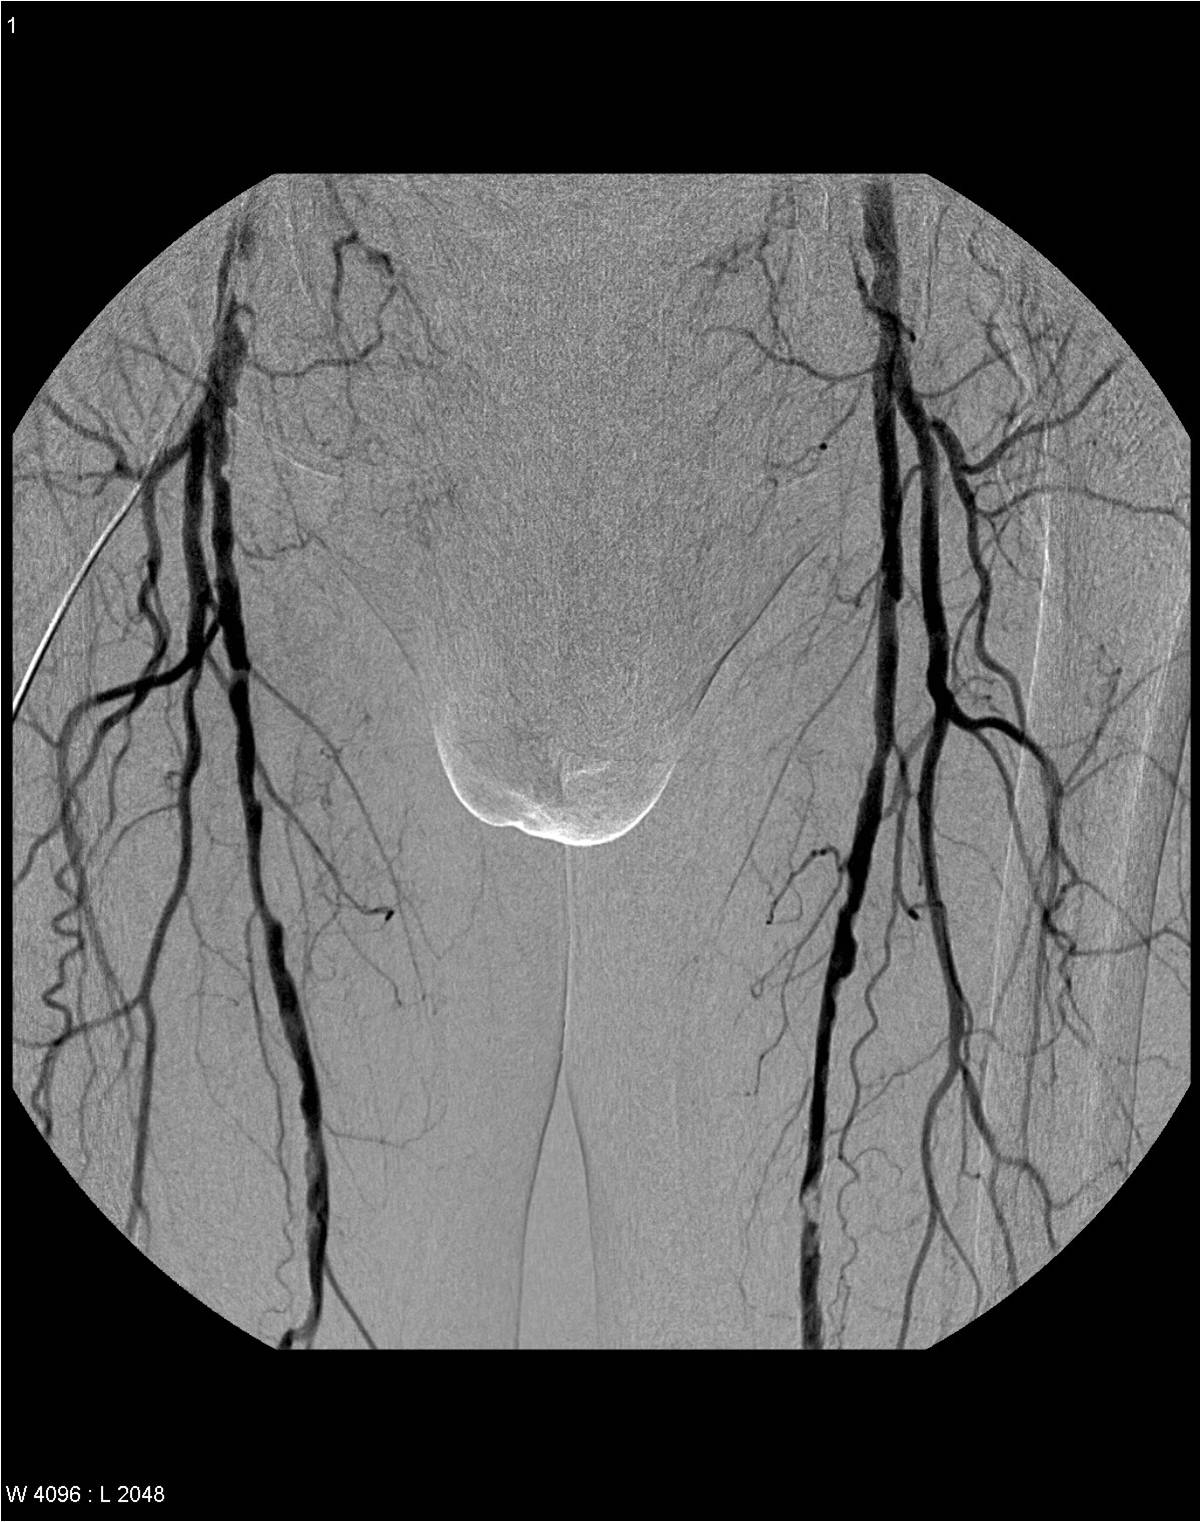

Usual imaging diagnostic approach is by catheter angiography, DSA technique if possible. This is carried out by repeated injections of smaller quantities of dye, which eventually can demonstrate the whole arterial system and the arterial outflow (on the late phase) even at territories with decreased flow speed vascularization.

The advantage of DSA is that smaller branches and collaterals can also be visualized well; it provides hemodynamic information and gives the opportunity for balloon catheter dilatation or stent implantation if needed. If the femoral arteries are not suitable for catheterization, the brachial artery can also be used as an alternative. Stenotic lesions can be semi-quantitatively categorized: below 50% - mild, 50-75% - moderate and above 75% - pronounced stenosis is determined.

Image

Proximal aortic occlusion – Leriche’s syndrome

Bilateral multiplex femoral artery stenosis

Fig. 20., 21.: DSA examination in lower extremity obliterative arterial disease